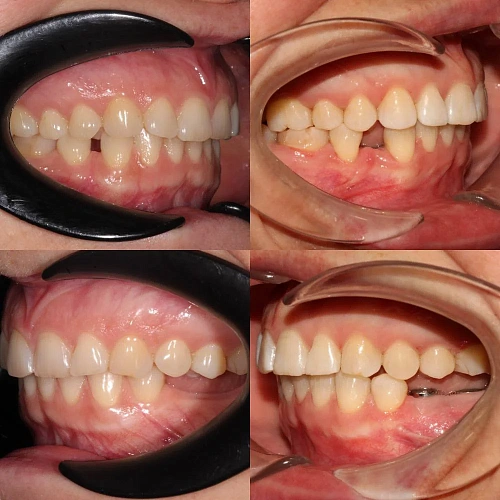

Исправление прикуса на брекетах за 28 месяцев перед протезированием

Неровные зубы, неправильный прикус.

Нарушение соотношения челюстей и неправильное положение зубов — ряды смыкались некорректно, зубы стояли со смещением.

Металлические самолигирующие брекеты H4 на обе челюсти. Выровнять зубы, исправить прикус, подготовить к установке коронок. Срок — около 2,5 лет.

Лечение заняло 28 месяцев (ноябрь 2023 — март 2026). После снятия брекетов пациентка направлена к ортопеду для установки коронок.

Проблема: Пациентка обратилась с жалобами на неровные зубы и неправильный прикус. Челюсти смыкались некорректно, зубы стояли со смещением. Часть зубов нуждалась в восстановлении коронками, но ставить их на кривой ряд с неправильным прикусом значит заведомо сократить им срок службы. Нагрузка будет распределяться неравномерно, и конструкции быстро выйдут из строя. Поэтому первый этап — ортодонтия, второй — протезирование.

Решение: Установили металлические самолигирующие брекеты H4 на обе челюсти. За 28 месяцев выровняли зубы и привели прикус в норму. После снятия брекетов зафиксировали ретейнеры на обе челюсти. Пациентка направлена к ортопеду — в течение недели устанавливает коронки, после чего будет проведено сканирование и изготовлены ретенционные капы уже по окончательному контуру зубов.